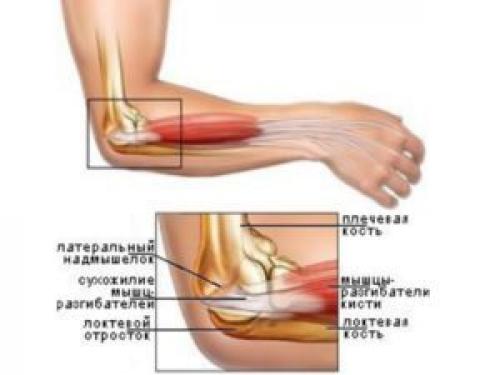

Растяжение связок

Резкие движения при занятиях приводят к повреждению сухожилий.

Травма чаще встречается у спортсменов и характеризуется частичным или полным разрывом соединительных волокон. Состояние возникает при следующих неблагоприятных факторах:

- движение в виде рывка;

- падение на верхние конечности;

- занятия экстремальными видами спорта, где доминирует нагрузка на руки.

Растяжение связок в локте проявляется следующим образом:

- боль с наружной или внутренней стороны;

- отечность и гематома;

- ограниченность подвижности;

- вывих локтевой кости, если произошел разрыв связок.